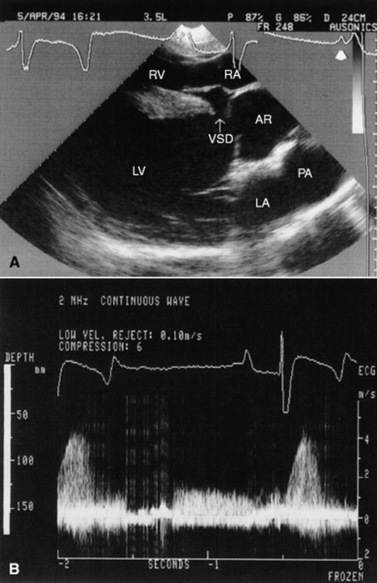

Clinical Pathology

Echocardiography is the diagnostic technique of choice for identifying a VSD. With two-dimensional echocardiography the VSD can be imaged directly (Fig. 30-5) and the shunt size, location, and direction demonstrated with pulsed wave Doppler, continuous wave Doppler, color flow echocardiography, or the injection of microbubbles. Careful scanning of the interventricular septum should be performed with two-dimensional echocardiography to directly image the VSD and measure its maximal diameter in two mutually perpendicular planes.31,32 The typical membranous VSD (≤2.5 cm in both planes) is missed if the long-axis view of the left ventricular outflow tract is not examined. The membranous VSD is located underneath the septal leaflet of the tricuspid valve and the right or noncoronary leaflet of the aortic valve. If a membranous defect is not found, the entire septum should be carefully scanned in all imaging planes to detect the VSD. The subpulmonic location, more common in calves, is easy to miss. This defect is usually best imaged in the short-axis view, scanning the interventricular septum between the left and right ventricular outflow tracts. With a left-to-right shunt a high-velocity turbulent jet is depicted from the right parasternal window, originating in the left ventricle, traversing through the hole in the interventricular septum into the right ventricle with color flow Doppler echocardiography (blood flow toward the transducer), whereas a negative contrast jet is imaged in the right ventricle with a right-sided injection of microbubbles.31,32 A left ventricular injection of microbubbles is necessary to visualize echo-laden blood in the right ventricle with a typical VSD. M-mode echocardiography may show septal discontinuity when traversing the ventricular septum from the apex of the heart to the aortic root (septal dropout). Moderate to large VSDs show left atrial and left ventricular enlargement, right ventricular enlargement, and pulmonary artery dilation. The left atrial—to—aortic root ratio is increased. Aortic valve prolapse and aortic regurgitation may also be detected because of loss of support of the aortic root from the VSD. Myocardial dysfunction and subsequent CHF may occur with a large VSD. Continuous wave Doppler echocardiography can be used to noninvasively assess the hemodynamic significance of the shunt (see Fig. 30-5, B). A peak shunt flow velocity of greater than or equal to 4 m/sec indicates a restrictive VSD with normal or near normal right ventricular pressures. Nuclear angiocardiography can also be used to demonstrate simultaneous opacification of the left and right ventricles. The radiographic presence of cardiomegaly and increased vascularization of the lungs provides only nonspecific evidence of VSD. If polycythemia is found, a complicated VSD should be suspected.

image

Fig. 30-5 Two-dimensional echocardiographic image (A) and continuous wave Doppler spectral tracing (B) of a ventricular septal defect (arrow) in a weanling colt. The ventricular septal defect (VSD) is located just underneath the septal leaflet of the tricuspid valve and right coronary cusp of the aortic valve. The VSD is best imaged in this left ventricular outflow tract view. There is significant left ventricular enlargement in this colt. The right atrium (RA), right ventricle (RV), left ventricle (LV), left atrium (LA), aortic root (AR), and pulmonary artery (PA) are all visible in this view. The spectral tracing shows a peak shunt velocity of slightly under 4 m/sec in systole, with some turbulent flow (spectral broadening) also detected in diastole with a peak flow velocity of approximately 1.3 m/sec.